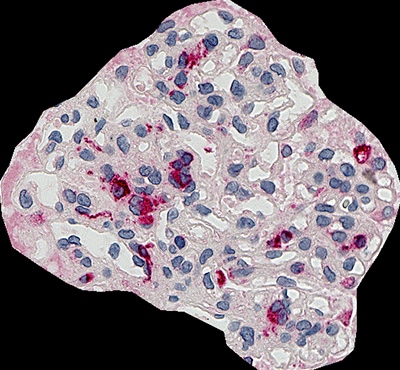

CD68(巨噬细胞)的肾小球占比分析事例

CD68(巨噬细胞)的肾小球占比分析事例如下所示。进行HE染色,拍摄肾脏活检的整体图像。通常情况下,我们很难对具有一定厚度的样本进行准确对焦,而借助Z栈拍摄,就能实现全幅对焦的清晰显微镜观察。

肾小球占比4.3%